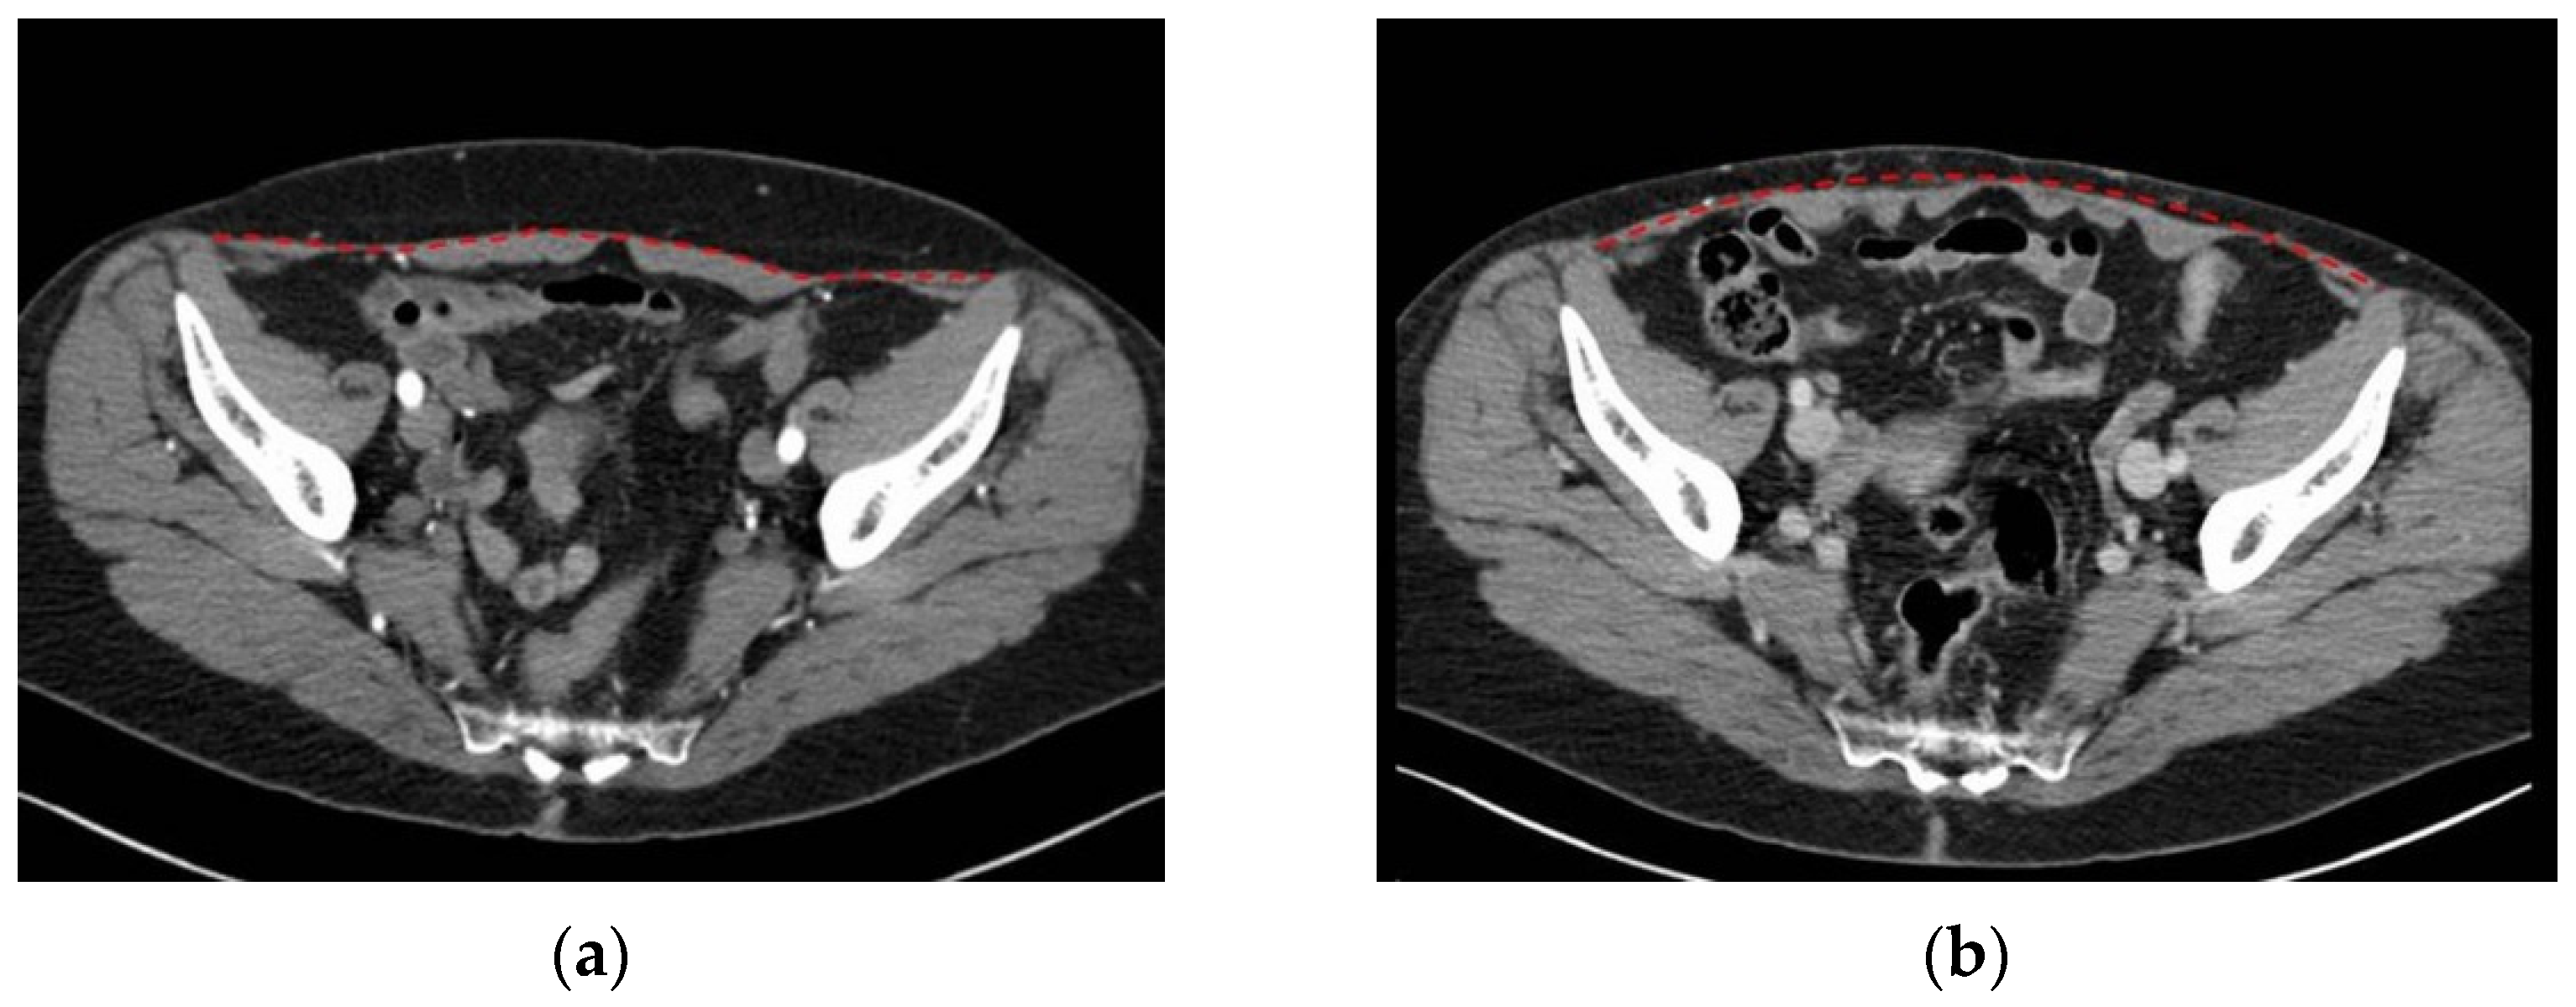

3.1. Two-Dimensional Evaluation